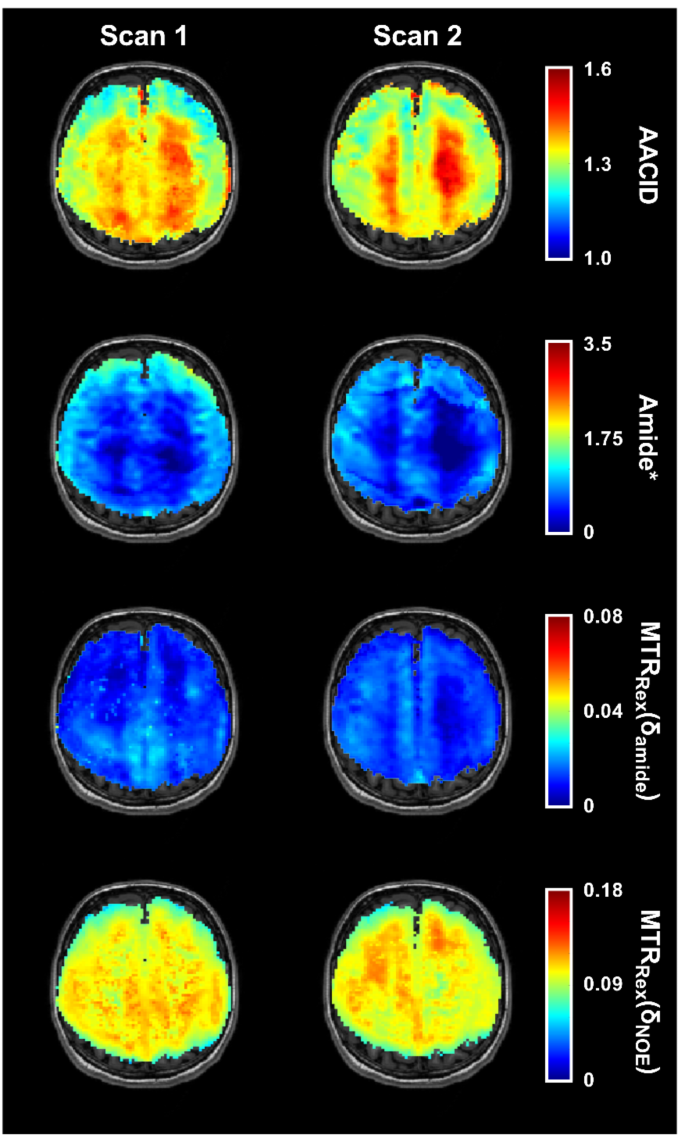

Figure 3 shows all the CEST contrast maps from one healthy participant from both the first scan and second scan for the same slice. Visually, the similarities between the two scans in both the GM and WM tissue is apparent for the calculated contrasts, with Amide* demonstrating the most visual differences. Figure 4 provides histograms of the distribution of all CEST contrast measurements in GM (top) and WM (bottom) for the same healthy participant showing the initial scan and second scan overlayed. Bland-Altman plots (Fig. 5) revealed negligible biases in all CEST contrasts.

Axial CEST contrast maps of one slice (corresponding to the center of the 3D volume) of one healthy participant. Amine/amide concentration independent detection (AACID), Amide*, MTRRex(δamide), and MTRRex(δNOE) maps of the same healthy participant for the first scan (left column) and second scan (right column), overlayed onto the corresponding T1-weighted axial slice (each scan approximately 10 days apart).